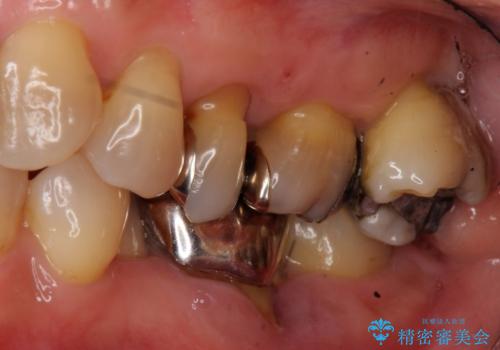

- 左下奥歯の歯ぐきの違和感で来院。

昔神経の治療をした歯が割れてしまっていました。

やむなく抜歯になりましたが、その部分にインプラントを始め希望されましたが、炎症により、骨がなく、かつ歯並びの関係で入れても歯ブラシができずにインプラントも長くもたなそうという診断になりました。